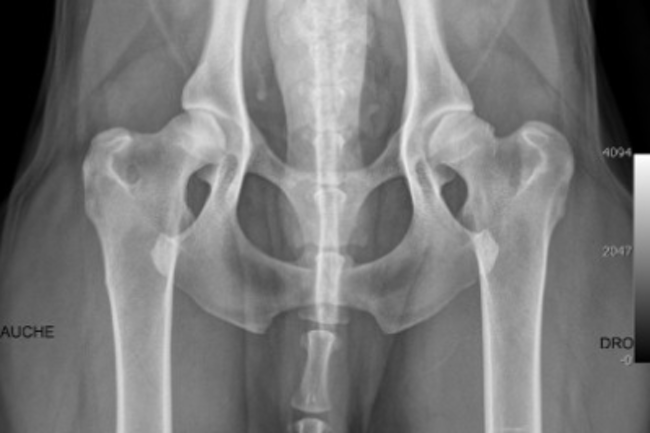

Je dois adopter une petite chienne cocker dans 2 mois. J’ai fait les démarches de réservation en envoyant un chèque qui s’avère être des Arrhes. Aujourd’hui une information supplémentaire s’est ajoutée sur le site de l’élevage concernant la mère des chiots, elle a une dysplasie de type C donc légère. Le père lui est de type B donc presque normal. C’est une maladie qui est héréditaire, par conséquent les chiots ont 50% de chance de présenter cette maladie.